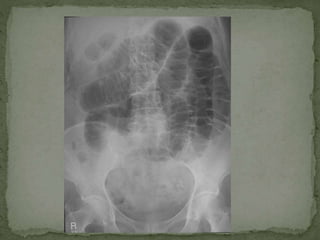

 Large bowel obstruction: Distension, colicky pain,

absolute constipation, N+V (faeculent), tinkling BS

 CXR CHEST/ ABDOMIN

 Simple Investigations: Bloods tests (FBC, U&E, LFT, amylase, clotting, CRP, G&S/ ABG)  Urine dipstick  Pregnancy test (all women of child bearing age with lower abdominal pain)  CXR CHEST/ ABDOMIN  ECG  More ADVANCE investigations:  Contrast studies  Endoscopy (OGD/colonoscopy/ERCP)  CT  MRI